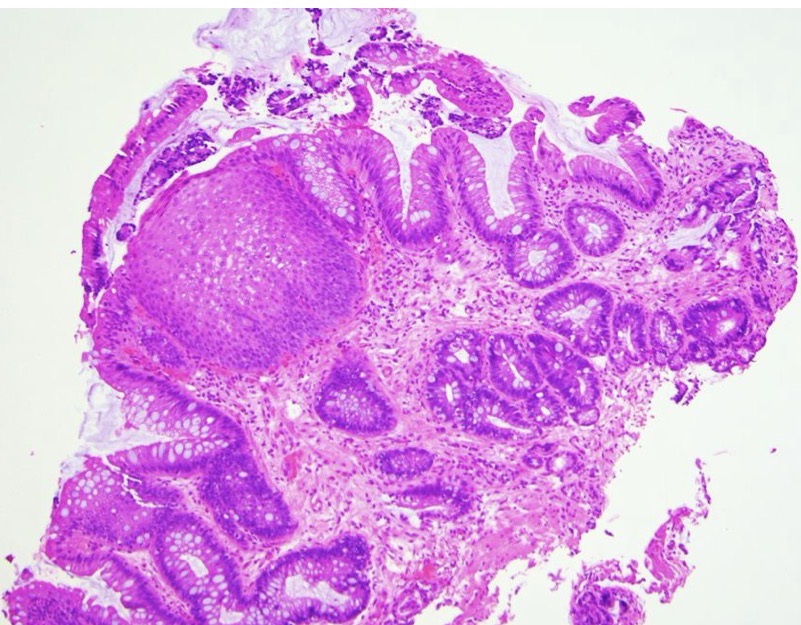

A- identify

B- describe

C- originate from ?

A- Colonic adenoma

B- Tubular colonic adenoma consisting mostly of round or oval glands

C- from benign epithelial tissue